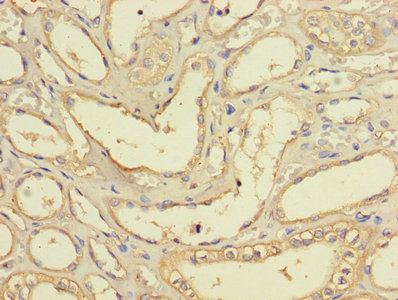

Immunohistochemistry of paraffin-embedded human kidney tissue using CSB-PA002798LA01HU at dilution of 1:100